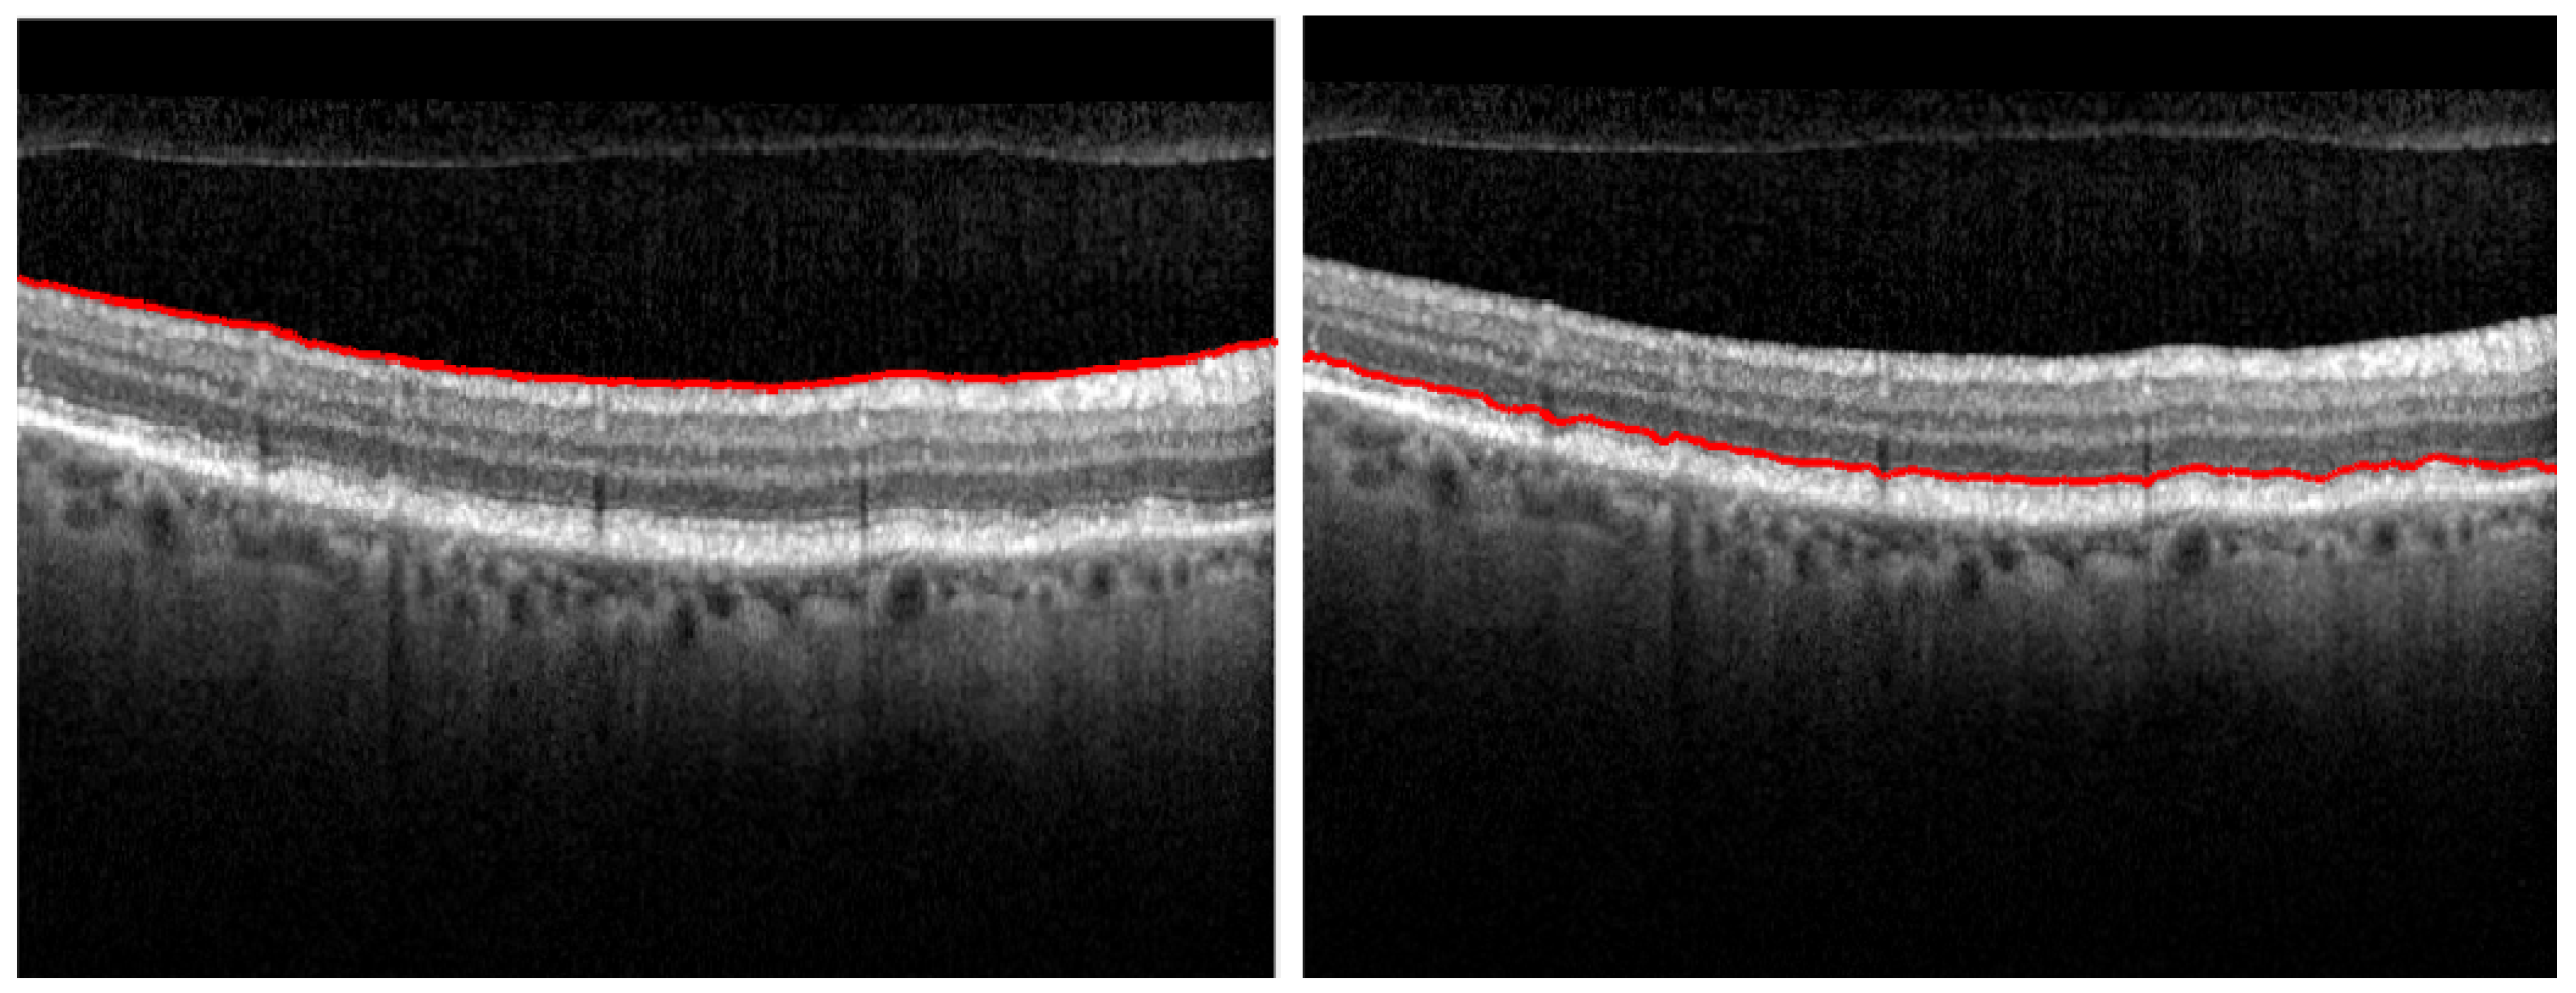

Even though the OCT B-scan’s accuracy of correctly representing the individual retinal layers is almost comparable to in vivo histopathology (Figure 8), manually delineating these layers is a time consuming task that can’t be fitted in a regular clinical practice routine.

Figure 8. Comparing the results of manual segmentation (left) to automatic segmentation (right) on a healthy retina (top) and on a retina with condition (bottom).

Diagnostics 12 00022 g008